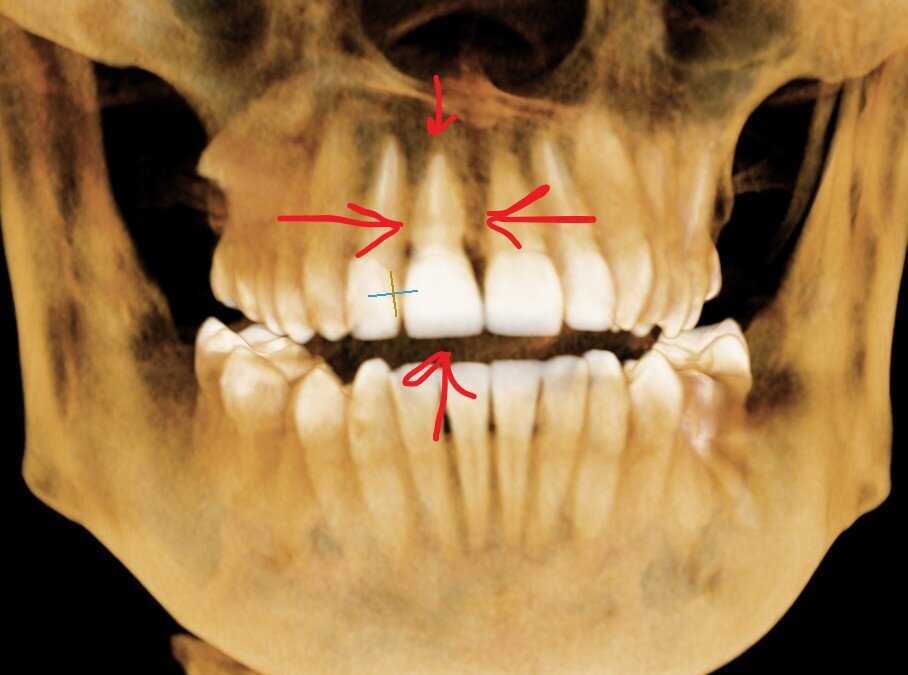

3Д визуализация костных структур и зубов.

Зуб ранее пролечен эндодонтически (нерв убит, каналы пройдены), покрыт коронкой.

Шах и мат - коронка не спасает от перелома, можете сказать вы. Но тут всё сложнее, перелом случился в области корня. Почему? Да кто его знает. Но выглядело всё так себе в поддесневой зоне.

Зуб 1.1, перелом корня.

Явно, что некоторые кариозные процессы "подразъели" корень под коронкой. Мы при протезировании не присутствовали, процесс не видели. Поэтому оценку не даём произошедшему. О причинах не гадаем.

Есть факт - деструкция тканей корня.

Вот в этом "тонком" месте и произошел перелом.

Новости для пациента печальные - такое не лечится. Слишком глубоко проходит линия перелома, слишком сильно поражён корень, слишком велика деструкция кости вокруг линии перелома.

Процессы разрушения корня, судя по всему, шли давно - деструкция коснулась кости. Наблюдаем её дефицит.